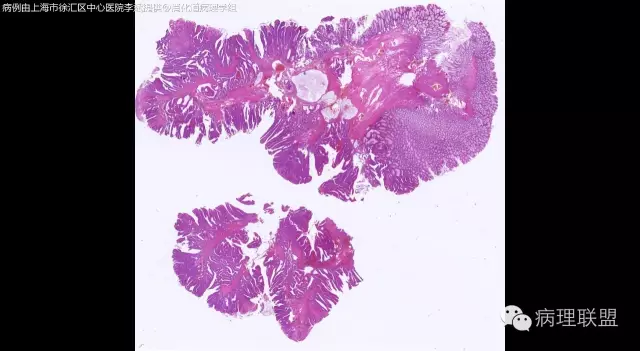

男,64岁,距肛门口45cm息肉大体:灰白结节2*2*1cm(病例由上海市徐汇区中心医院 李斌 提供,致谢!)

管状~绒毛状腺瘤伴低级别上皮内瘤变,黏膜下层部分腺体破裂黏液外溢伴黏液糊形成。

本例部分腺体异位到黏膜下层。